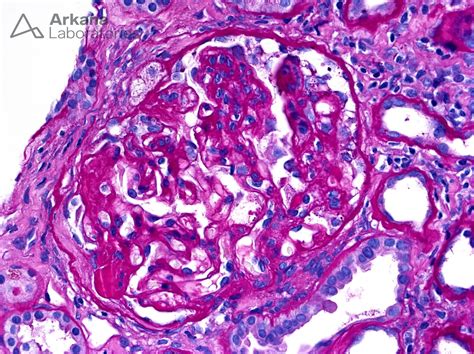

The term Focal Segmental Glomerular sclerosis describes a specific pattern of damage. "Focal" means that only some of the glomeruli are scarred, while "segmental" indicates that only a portion of each individual glomerulus is affected. Glomeruli are the tiny units in your kidneys responsible for filtering waste and excess fluids from your blood. When these units become scarred, they cannot function correctly, which may lead to the leakage of protein into the urine, a condition known as proteinuria.

Kidney Biopsy The gold standard to visualize scarring under a microscope.